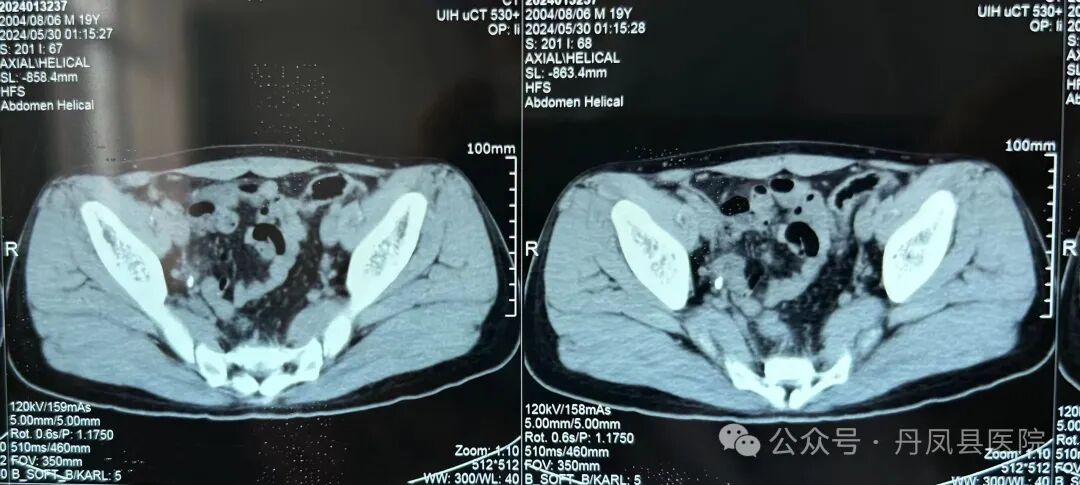

病例二

患者周某,男,19岁,以“右腰部阵发性绞痛2天”主诉入院。泌尿系CT示:右侧输尿管中段结石1.2*1.1cm大小。经过完善的术前准备,于2024年6月3日在全麻下行输尿管镜钬激光碎石,结石粉沫化,术程顺利,恢复良好。